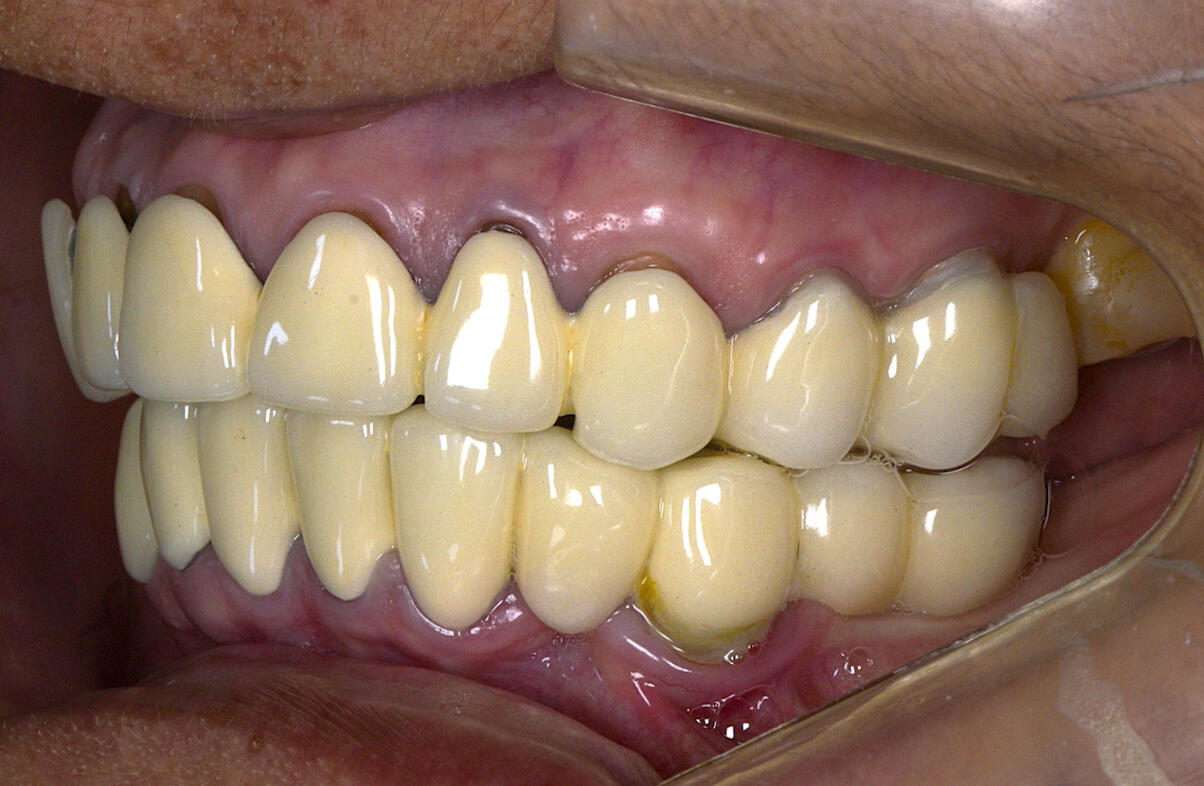

Complex Prosthetic Rehabilitation in an International Patient with Prosthetic Failure and Periodontal ComplicationsA patient from the state of Georgia (United States) sought specialized dental treatment due to complex failure of existing fixed dental prostheses. Clinical examination revealed prosthetic fractures, gingival inflammation, food impaction, compromised periodontal support tissues, and disruption of the smile line and occlusal harmony.A comprehensive prosthetic and periodontal treatment protocol was implemented, focusing on biological compatibility, functional occlusion, periodontal stabilization, and esthetic reintegration. Advanced restorative techniques and biomaterials were utilized to ensure long-term functional and biological stability.Post-treatment outcomes demonstrated improved periodontal health, occlusal function, and esthetic balance of the smile.This international case reflects transnational recognition of clinical expertise and highlights the importance of high-level interdisciplinary restorative and periodontal rehabilitation in complex prosthetic failures.